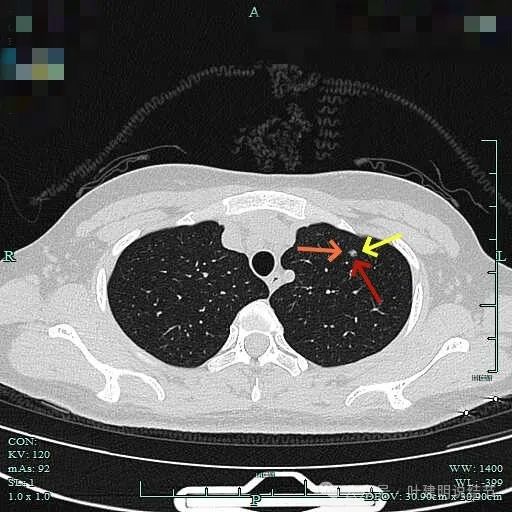

非薄层平扫上病灶位于左上叶,仅约4-5毫米,磨玻璃密度,轮廓与边界清,实性成分不明显,但并不太淡。

薄层上病灶出现,点状,边缘不光滑。

轮廓清,有微小血管走向病灶,表面并不光滑。

灶内密度也不均匀,微小血管走向病灶。

病灶内局部似有小空泡或局灶细支气管扩张,有血管贴边进入,整体轮廓与边界较清。

边缘区小血管似乎有拐了个弯,是不是病灶的影响导致的?